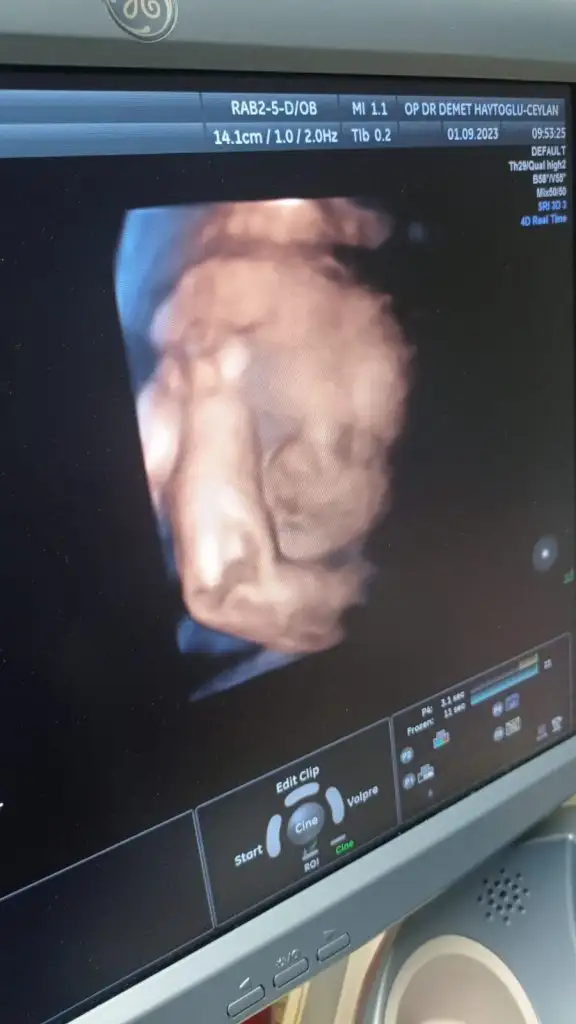

Biz de kontrolden geldik teyzeleerrr. 1739 gram 40 cm boyu olmuş tosunun. Haftasından 1 hafta önde karpuz yemeyi azalt böyle giderse normal doğuramayacaksın dedi doktoru :KK53: Normal istersem en fazla 9 kasıma kadar bekleyecekmiş, ama bizim sıpa dönmemiş henüz. Kafası tam midemin altında, mide yanmalarım ondan oluyomuş. Aynı bana benzemiş şükür:KK49:Sezaryen olursam da bu bebiş Ekim bebitosu olacak.

WhatsApp Image 2023-09-01 at 11.11.16.webp

Bunu da ekleyeyimmmm.